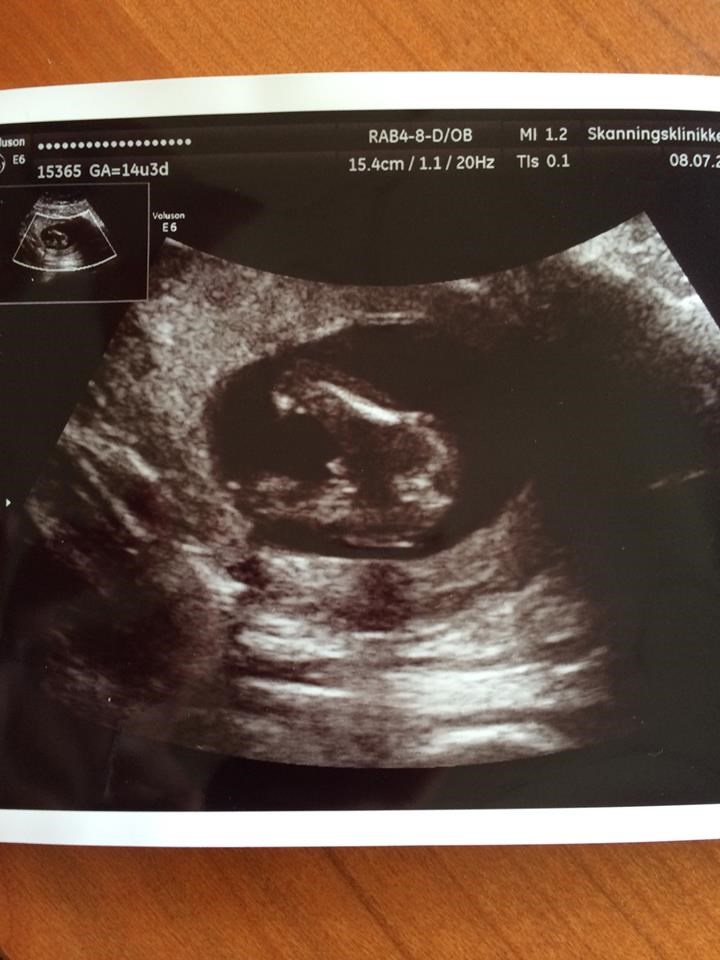

CharlotteA

Der hvis ingen tvivl her..

Vedhæftede fotos (klik for at se i fuld størrelse)